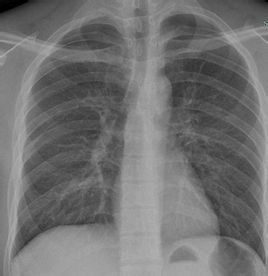

肺紋理主要是由肺動脈、肺靜脈構成的影像,支氣管、淋巴管也參與肺紋理的構成。在病變時,肺靜脈、支氣管、淋巴管在形成肺紋理的影像上比正常時占的比重要大,因此肺紋理增強從形態上看大體可分為三種。

一是肺紋理粗大,邊緣較清楚,從肺門向肺野保持血管走向特徵的肺紋理增強,常見於風濕性心臟病、房室間隔缺損、動脈導管未閉、心力衰竭等;

二是肺紋理較細,分支較少,邊緣清楚,其中夾雜變形的肺紋理和蜂窩影像的肺紋理增強,常見於慢性支氣管炎、支氣管擴張等;

三是在肺野內呈纖網、網狀的紋理增強,常見於粟粒型肺結核、塵肺(矽肺)、癌性淋巴管炎等。